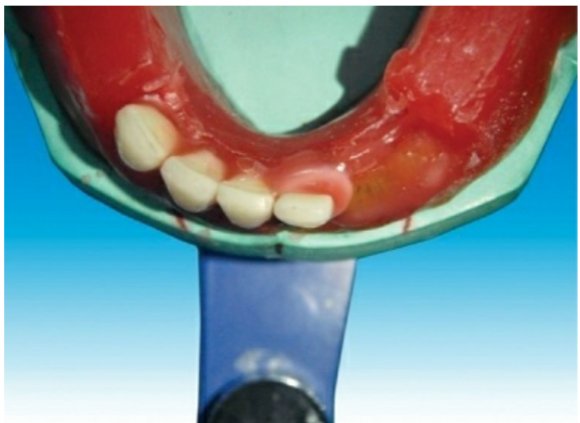

🔻The incisal edge of the mandibular central incisor should follow the outline

of the occlusal rim, and the incisal edge of the mandibular central incisor tooth

should not cross over the land area when viewed occlusally

When viewed from:

Front: Long axis inclines slightly towards the vertical axis.

Side: Slopes labially.

Occlusal plane: Incisal edge is 0.5–1 mm above the occlusal

plane

When viewed from:

Front: Long axis inclines towards the vertical axis.

Side: Slopes labially less than central incisor.

Occlusal plane: Incisal edge is 0.5–1 mm above the occlusal

plane

When viewed from:

Front: Long axis inclined towards midline.

Side: Slopes lingually.

Occlusal plane: Cuspid tip is 0.5–1 mm above the occlusal

plane

The mesial slope of the maxillary canine should overlap the distal slope of

the mandibular canine

🛑The vertical overlap (over bite) between the maxillary and mandibular

incisal edge should be 0.5–1 mm, and the horizontal overlap (over jet) between

the maxillary and mandibular incisal edges should be 1–2 mm.

🛑The horizontal overlap should be uniform from left maxillary to right maxillary canine